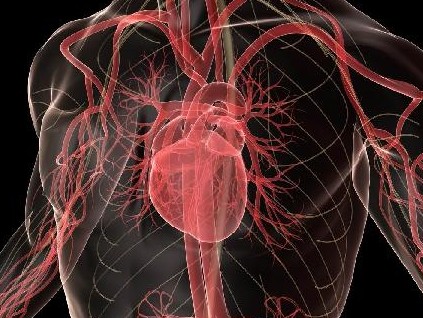

Σήμερα όμως που γνωρίζουμε τι ακριβώς συμβαίνει με τις στεφανιαίες αρτηρίες της καρδιάς, τα πάντα εξηγούνται. Οταν το τεστ κοπώσεως είναι αρνητικό (δηλαδή φυσιολογικό), αυτό δεν σημαίνει ότι οι στεφανιαίες αρτηρίες της καρδιάς είναι φυσιολογικές.

Αντίθετα, μπορεί οι στεφανιαίες αρτηρίες να έχουν στα τοιχώματά τους αθηρωματικές πλάκες γεμάτες κυρίως με χοληστερίνη μικρού ή ακόμα και μεγάλου μεγέθους.

Το τεστ κοπώσεως μπορεί να είναι φυσιολογικό όταν οι αθηρωματικές πλάκες είναι μικρού μεγέθους αλλά ακόμα και μεγάλου μεγέθους, στις περιπτώσεις εκείνες όπου έχει αναπτυχθεί παράπλευρη κυκλοφορία.

Το έμφραγμα έχει σχέση με τη ρήξη των αθηρωματικών πλακών και μάλιστα των πλακών μικρού μεγέθους. Η χρόνια ισχαιμία του μυοκαρδίου οδηγεί σε καρδιακή ανεπάρκεια ισχαιμικής αιτιολογίας.

Αντίθετα, εάν θέλουμε να δούμε τις στεφανιαίες αρτηρίες και να εκτιμήσουμε το μέγεθος των αθηρωματικών πλακών, προσφεύγουμε στην αξονική τομογραφία των στεφανιαίων αρτηριών (αξονική στεφανιογραφία).